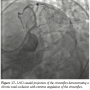

Case 5. A distal lesion in a small posterolateral vessel was successfully treated after very deep engagement of the GuideLiner catheter (Figures 14–16). In the past, this lesion would either be treated medically or with balloon angioplasty, but with the availability of drug-eluting stents in smaller diameters (2.25 mm) and low late loss of 0.1 mm, these patients can be offered relief of their angina as was demonstrated in this case. Caution needs to be exercised with such maneuvers with the catheter.

Case 6. This case demonstrates the utility of the GuideLiner catheter in coaxial alignment for delivering stents even in very proximal coronary segments because of difficulties related to extreme proximal vessel tortuosity. An extremely angulated take off of the left circumflex artery off the left main coronary artery was dealt with by placing a GuideLiner catheter into the distal left main. Even though the GuideLiner did not actually enter the circumflex artery, it provided enough support for the delivery of a drug-eluting stent to treat the entire proximal stenosis successfully with one stent (Figures 17–19).

In the third, fourth, and fifth cases, the reason for the development of this device, facilitating distal stent delivery, is demonstrated. Commonly used methods to overcome difficulty with stent delivery include straightening of the vessel with a buddy wire, use of an anchor balloon, and using large diameter guiding catheters with more supportive curves. The GuideLiner facilitates delivery of stents to distal segments of the coronary vessel (Figures 4 and 5) by allowing safe deep vessel intubation. This provides the necessary extra back-up support needed for stent delivery. In an era when radial artery intervention is making a comeback into the mainstream, this may have added significance because the vast majority of cases via the radial artery are performed with 6 Fr guiding catheters. Also because of the angle of entry from the radial approach into the aortic sinus, coaxial guide placement is difficult. The GuideLiner catheter may allow for maintaining coaxial guide orientation. In case 3, a long circumflex artery stenosis was treated with deep engagement of the GuideLiner catheter to deliver 2 long DES as opposed to several shorter length drug-eluting stents. This may have incremental value in an era of cost containment by treating long lesions with fewer drug-eluting stents, thus lowering the cost per case.

With this technique, use an inflated low profile balloon or a microcatheter on the wire while the catheter is advanced into the coronary artery. This reduces the dead space between the GuideLiner catheter and guidewire, providing a tapered, atraumatic leading edge. It also stiffens the rail over which the device can be advanced. This decreases the incidence of coronary dissections in the proximal vessel. An extension of this concept involves using the GuideLiner catheter even with aggressive guiding catheters, especially when there is a need for delivery of long stents to distal portions of the vessel. This is amply illustrated in cases 4 and 5 of this series. When delivering stents to distal parts of the vessel, caution needs to be exercised when the metal collar of the GuideLiner extends past the secondary curve of the guiding catheter. This is the basis for the recommended deep seating distance of 10 cm from the tip of the guide. If necessary, deeper engagement (>10 cm) can be performed without risk to the vessel or the patient.